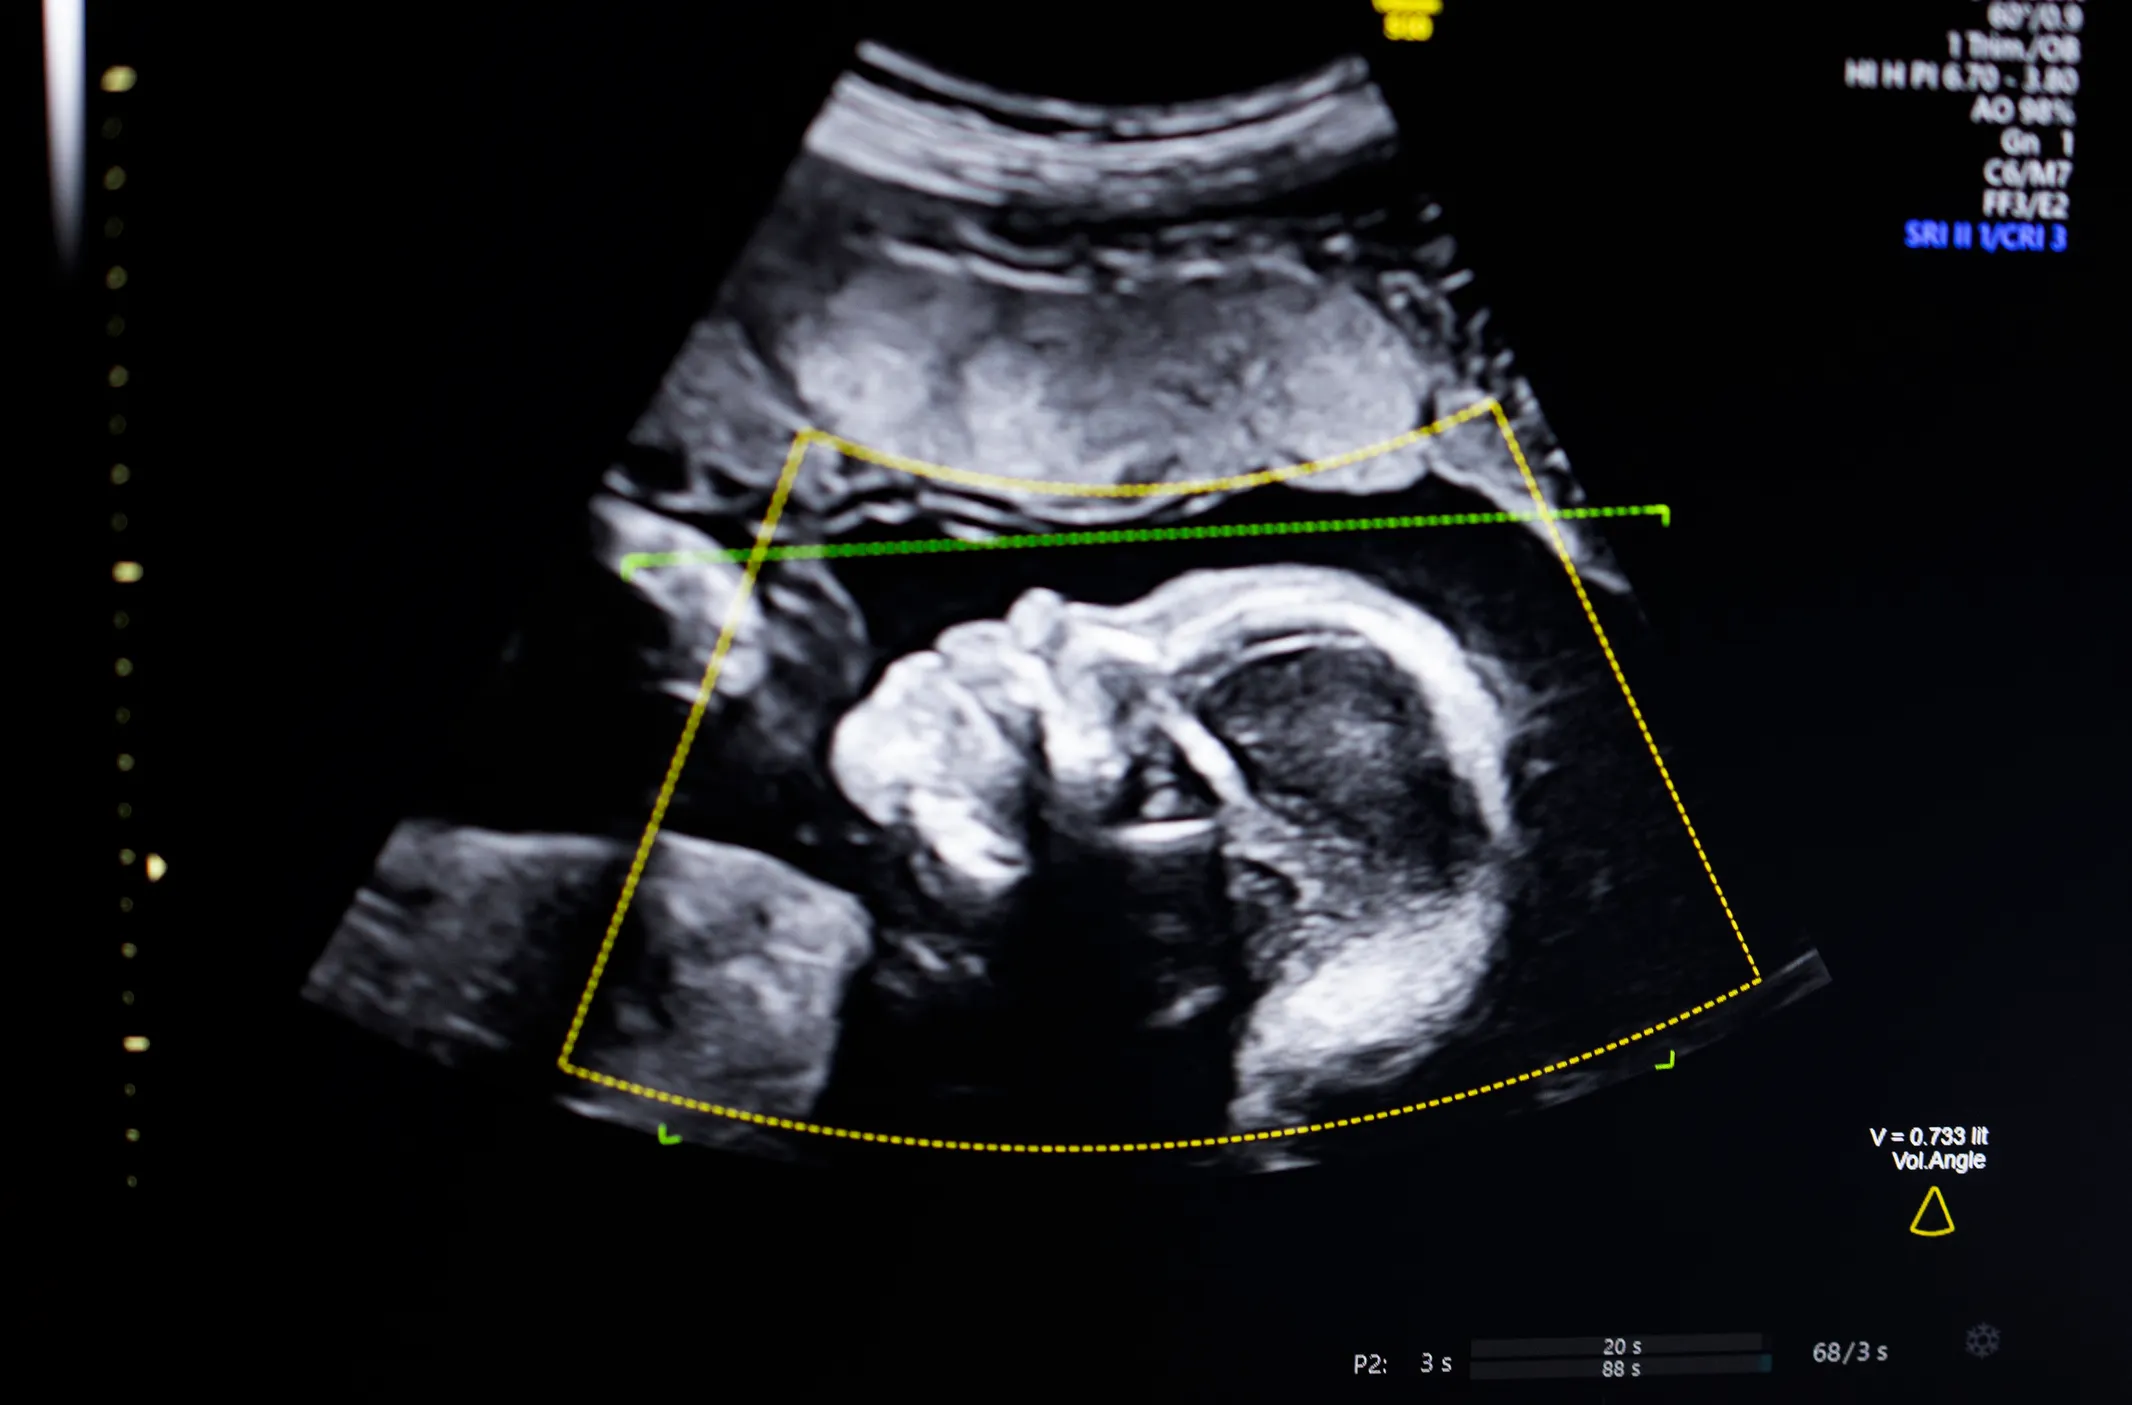

현재 미국을 포함한 전 세계 산전 초음파 검사에서 태아 기형의 약 절반가량이 숙련도 부족이나 이미지 품질 문제로 인해 오진되거나 간과되고 있습니다. 바이오틱스 AI는 이러한 비극적인 수치를 획기적으로 낮추기 위해 탄생했습니다. 이번 FDA 승인은 AI가 의료진의 ‘두 번째 눈’이 되어 산모와 아이 모두에게 더 안전한 미래를 제공할 수 있음을 증명하는 사례입니다.

바이오틱스 AI의 소프트웨어는 단순히 이미지를 보여주는 것을 넘어, 실시간으로 초음파 영상을 분석하여 의료진에게 결정적인 정보를 제공합니다.

1. 컴퓨터 비전 기반 실시간 피드백 (H3) 이 시스템은 초음파 기기에 연결되어 검사 과정에서 표준 해부학적 뷰가 제대로 캡처되었는지 실시간으로 확인합니다. 만약 중요한 부위가 누락되거나 영상의 질이 낮을 경우 즉시 알림을 주어, 검사 완성도를 기존 70% 수준에서 90% 이상으로 끌어올립니다.

2. 방대한 데이터 학습과 높은 신뢰도 (H3) 바이오틱스 AI는 다양한 인종과 체형을 포함한 약 11,000건 이상의 고품질 초음파 데이터를 학습했습니다. 이를 통해 태아의 척추분리증이나 신장 발육 부전 등 300여 가지 이상의 태아 증후군을 98%의 높은 정확도로 감지해냅니다.